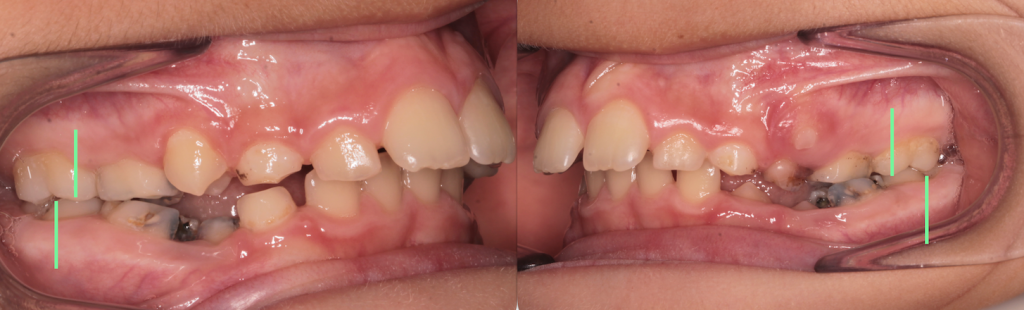

Il paziente si presenta alla mia osservazione con un rapporto di seconda classe (dove la mandibola è più indietro della mascella) che si manifesta con il molare superiore più avanti del molare inferiore (per farti capire meglio: le righe verdi dovrebbero essere allineate, quindi il molare superiore più avanti o quello sopra più indietro).

Sono presenti inoltre delle carie (sui denti da latte), che abbiamo deciso di non curare perché non c’era dolore, sarebbero caduti nel giro di qualche mese e il paziente non era troppo collaborante!)

Consegniamo l’apparecchio ortodontico miofunzionale con indicazione di portarlo qualche ora durante il giorno per le prime due settimane (per abituarsi a tenerlo senza perderlo tutta la notta) e tutta la notte. Ecco i risultati dopo 3 mesi di apparecchio.